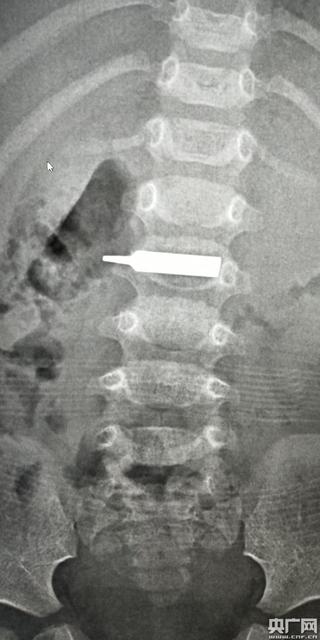

3、异物在食管内停留时间过长,或尖锐异物的直接损伤,而发生食管炎、食管脓肿、食管穿孔、纵隔感染、食管器官瘘、化脓性胸膜炎等并发症。还可出现发热、脱水、呼吸困难及全身中毒症状。

4、有时尖锐异物(小骨碎片或鱼骨刺)可直接穿透食管壁,穿破主动脉或心包,引起消化道大出血或心包化脓,有极大危险性。

5、多数异物在胃肠道内长期存留而不引起任何症状,偶有腹部不适或痉挛性腹痛。

6、尖锐的异物可损伤胃肠粘膜而引起肠道出血,但很少发生胃肠穿孔,如果穿孔症状变现缓慢,无急性腹膜炎的症状和体征。